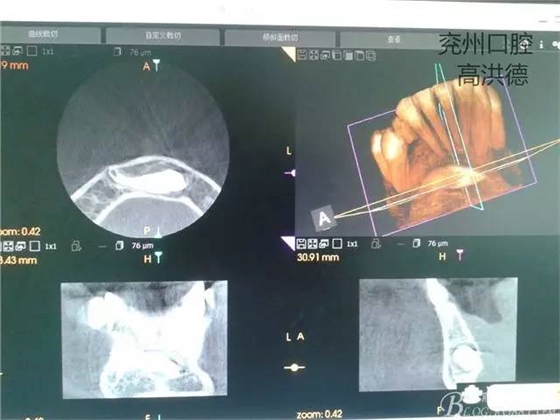

三維成像

矢狀位

冠狀位,舌側(cè)觀